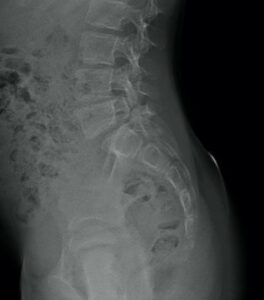

Le spondylolisthesis L5 est un glissement en avant de la 5° vertèbre lombaire par rapport au sacrum. Le glissement est du à une fracture progressive (lyse) à la jonction (isthme) entre la partie antérieure et la partie postérieure de la 5° vertèbre. D’où le nom de spondylolisthésis par lyse isthmique.

Spondylolisthésis stable